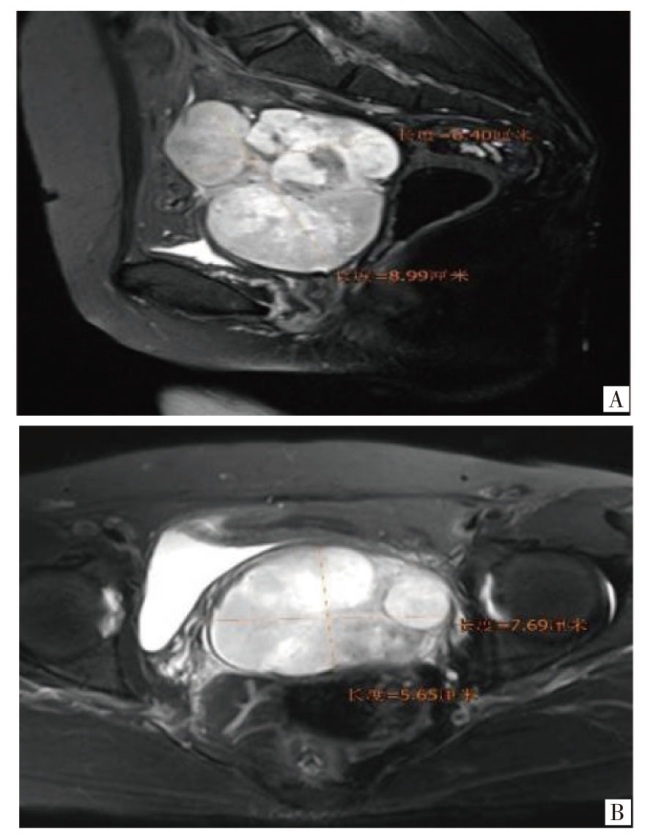

报告1例原发于宫颈的未分化子宫肉瘤病例。患者因绝经7年,阴道出血1周就诊,妇科检查触及宫颈9 cm大小的肿物,影像学检查提示宫颈巨大肿物及盆腔积液,未见明显肿大的淋巴结。遂行经腹全子宫切除术+双侧输卵管卵巢切除术,术后病理活检及免疫组织化学检查提示低级别未分化子宫肉瘤。术后患者拒绝放化疗,未定期复查。半年后再次因阴道出血,下腹部胀痛就诊,影像学提示阴道残端占位性病变,考虑肿瘤复发可能,遂行经导管髂内动脉栓塞术+髂动脉造影+动脉注射化疗药物(顺铂60 mg+表柔比星30 mg)。2个月后又因间断阴道出血在外院化疗1次。定期随访9个月,期间未行治疗,间断阴道出血。后失访。

A case of primary undifferentiated uterine sarcoma of the cervix is reported. The patient presented for medical consultation due to vaginal bleeding for 1 week after 7 years of menopause. A 9 cm mass in the cervix was detected during a gynecological examination. Imaging studies indicated a huge cervical mass and pelvic effusion, with no obvious enlarged lymph nodes. Subsequently, an abdominal total hysterectomy and bilateral salpingo-oophorectomy were performed. Postoperative pathological biopsy and immunohistochemistry suggested low-grade undifferentiated uterine sarcoma. After the operation, the patient refused radiotherapy and chemotherapy and did not undergo regular follow-up. Six months later, the patient presented again with vaginal bleeding and lower abdominal distension and pain. Imaging showed a space-occupying lesion at the vaginal stump, and tumor recurrence was considered possible. Therefore, transcatheter internal iliac artery embolization, iliac artery angiography and intra-arterial injection of chemotherapy drugs (cisplatin 60 mg + epirubicin 30 mg) were carried out. Two months later, the patient received chemotherapy once at another hospital due to intermittent vaginal bleeding. The patient was followed up regularly for 9 months, during which no treatment was administered, and intermittent vaginal bleeding occurred. The patient was then lost to follow-up.